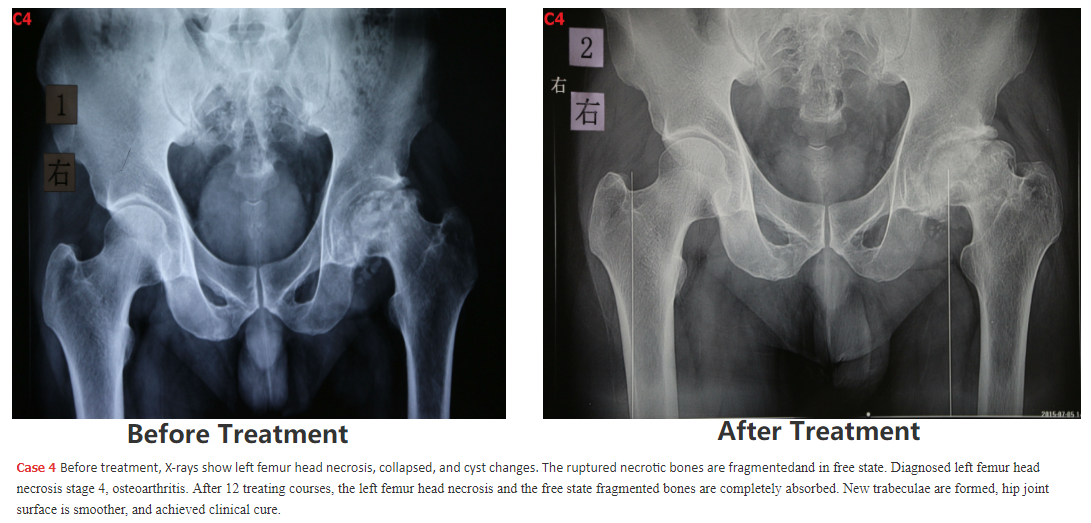

5. following are SOME Chinese patients we have cured - we will add the cases 5, 6, 7, 8, 9, 10, 11, 12.... SOON